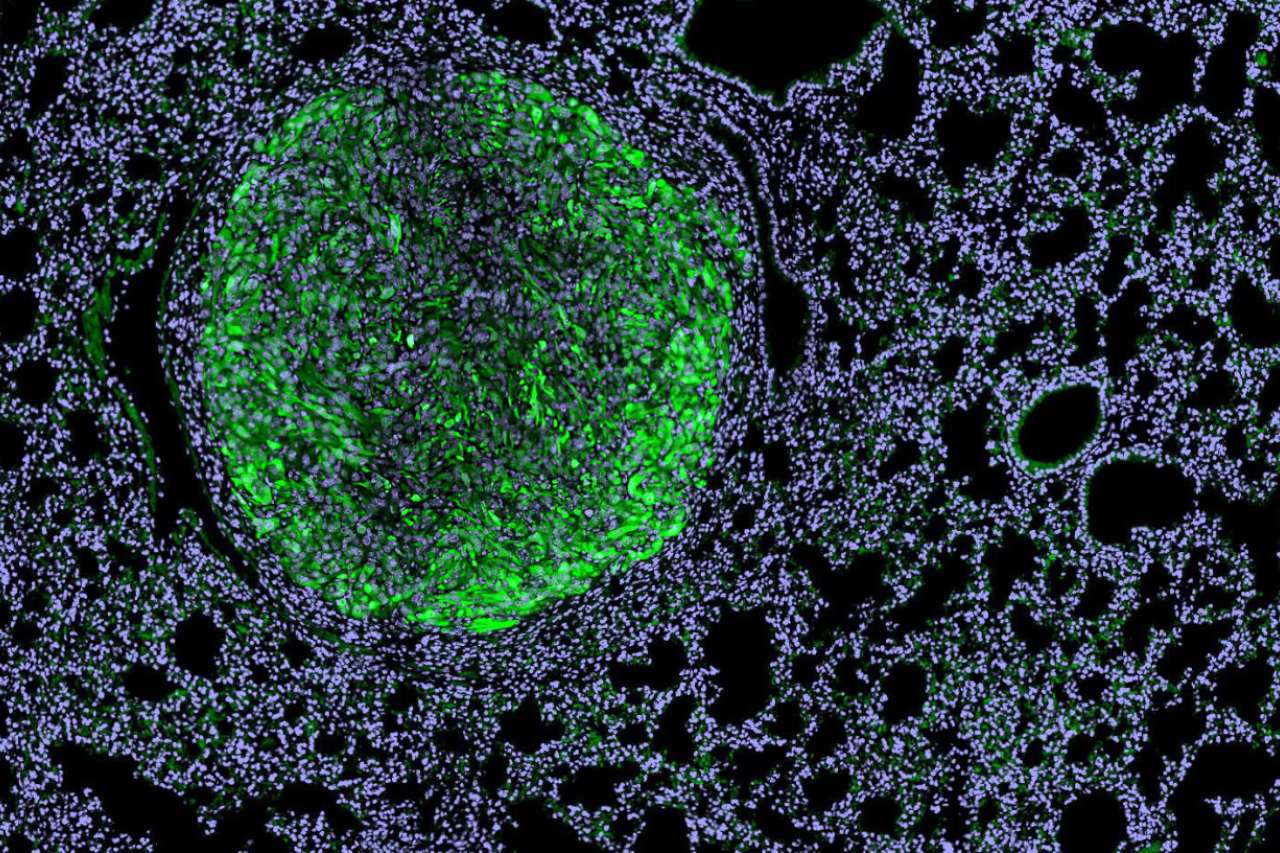

UCLA scientists develop off-the-shelf immunotherapy for metastatic kidney cancer

Dr. Arnold Chin, professor of urology, and Dr. Lily Wu, professor of molecular and medical pharmacology and urology at the David Geffen School of Medicine at UCLA, are co-senior authors on a new study that offers a promising next-generation strategy for treating metastatic renal cell carcinoma. UCLA researchers have developed a new kind of immunotherapy that uses specially engineered immune cells equipped with built-in weapons to attack kidney cancer tumors and reprogram their protective environment — all without the need to customize treatment for each individual patient.